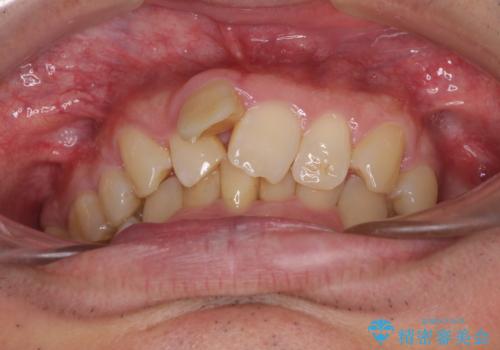

通常では速やかにオールセラミッククラウンにて補綴治療を行うのですが、デコボコしている歯列も気になっていたため、事前に矯正治療を行うこととしました。

上顎歯列の叢生が著しかったため、上顎左右第一小臼歯2本を抜歯し、目立たないワイヤー装置にて治療を進めることとしました。